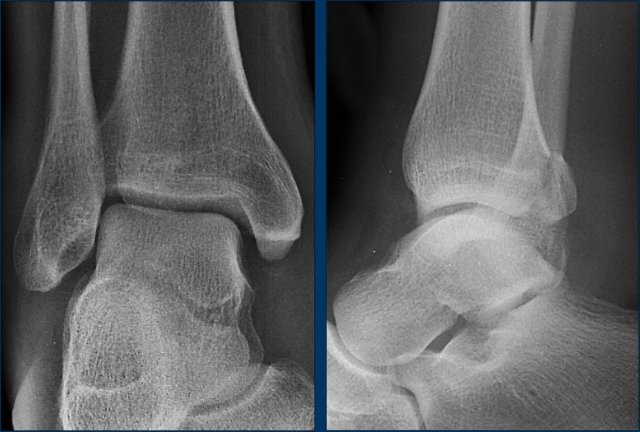

case 4 - distortion

This is another case of a nutcracker fracture as a result of compression on the lateral side of the tarsus due to eversion in Chopart's joint.

The eversion can also lead to distraction on the talonavicular side with either avulsion of the posterior tibial tendon or avulsion of the medial pole of navicular bone, where the tendon attaches, as was seen in case 2.